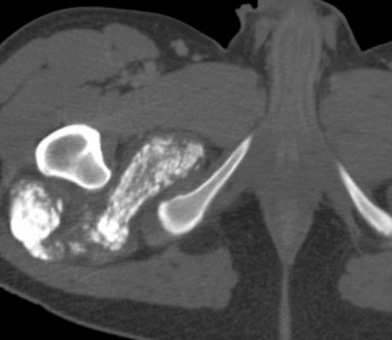

Rhabdomyosarcoma

• Pelvic RMS

• Peak incidence in childhood at age ~2-6 years

• Can occur from anywhere including bladder, uterus, vagina, etc